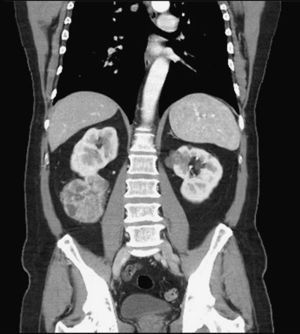

En nuestra serie se ha realizado abordaje ipsilateral y también contralateral, el cual planteaba mayores dificultades técnicas, como el cambio en la posición de los trocares y del paciente. Uno de ellos fue diagnosticado de neoplasia de colon y doble neoplasia renal, no descrito hasta ahora2,4-7. En este caso, se realizó primero la nefrectomía parcial izquierda por retroperitoneoscopia, con intención de mantener virgen la cavidad peritoneal para la siguiente intervención. Esta vía de abordaje no era aconsejable en el tumor derecho, dado su gran tamaño, que lo hacía técnicamente más complejo (especialmente debido a que la renorrafia por vía retroperitoneal resulta más complicada por la falta de espacio y triangulación). Días después se realizó la colectomía subtotal laparoscópica en decúbito supino, cambiándose a decúbito lateral izquierdo para la nefrectomía parcial derecha. A pesar del tamaño tumoral, debido al antecedente quirúrgico en el riñón contralateral, se planteó una cirugía conservadora de nefronas, con intención de preservar la función renal (fig. 1).